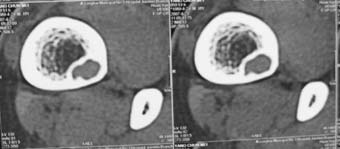

男,中学生打篮球时右踝扭伤,拍片时发右胫骨下端楕圆形透亮影,是不是动脉瘤样骨囊肿,请讨论

骨皮质内破坏区,其下部可能为“巢中有蛋“征,首先考虑骨样骨瘤,本病须与骨皮质脓肿,硬化性骨髓炎、骨梅毒等疾病鉴别。请结合临床进一步鉴别。

胫骨后外侧见囊样低密度边缘硬化,其内见小点状高密度影,首先考虑骨样骨瘤

应该是比较典型的非骨化性纤维瘤:病灶偏于骨干的一侧,紧靠皮质下,呈类圆形,靠近髓腔侧有硬化边,病灶长轴平行于骨干,周围无骨膜反应和软组织肿块。与骨样骨瘤鉴别:后者具有明显或剧烈疼痛,“瘤巢”为其特征,在瘤巢周围有显著的反应性骨质增生。